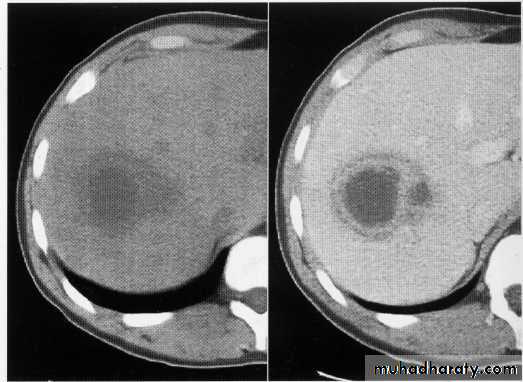

hepatic mets

hepatic mets,arterial phase

hepatic mets venous phase